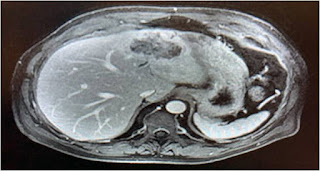

A male patient in seventh decade presented to emergency with obstructed umbilical hernia that got spontaneously reduced. He was well controlled diabetic on Injection insulin. There was history of heavy tobacco use for over 3 decades. During work up for elective laparoscopic umbilical hernia repair, abdominal CT scan was performed which revealed a large mass lesion in left hepatic lobe. A subsequent triple phase contrast enhanced MRI scan showed 7 x 5 cm lesion in segment 2, 3 & 4 of the liver that showed initial rim enhancement and then progressive and centripetal enhancement after the administration of intravenous contrast material with associated capsular retraction (Figure 1).

Figure 1. Triple phase MR scan of liver

Based on characteristic MRI scan findings, a diagnosis of IHC was made.